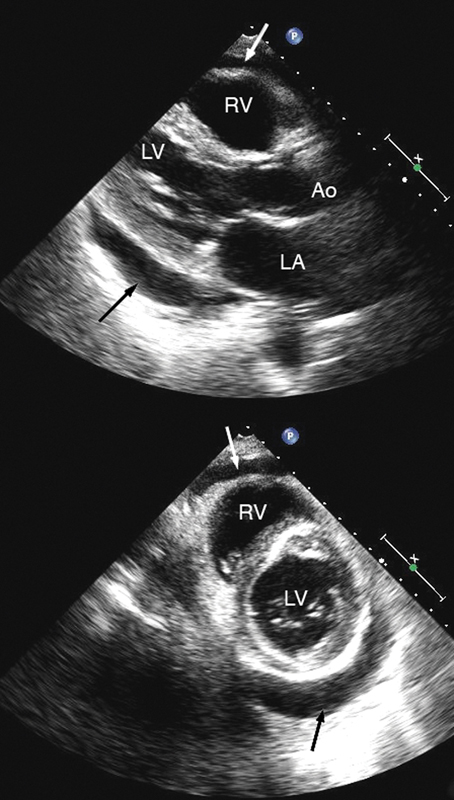

فحوصات تشخيصية لبعض امراض القلب والشرايين التاجية